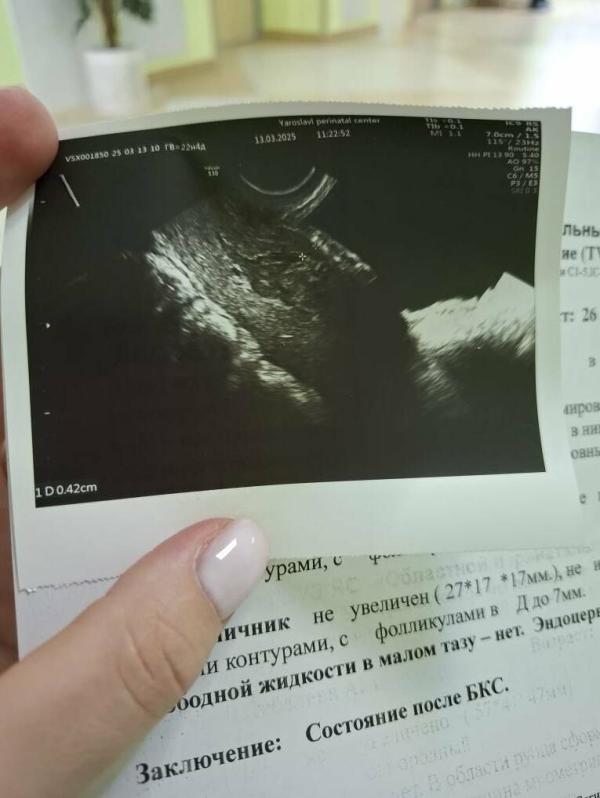

Была на плановом приёме у гинеколога после кс, отправила на узи и там сказал врач, что сам шов срастается, а вот матка сраслась не до конца (узист сказал, просто мало времени прошло, повторное узи через пол года) и на фоне этого гинеколог настоятельно рекомендует средства контрацепции, так как матка до конца не сраслась плюс нет менструации и вероятность забеременеть очень велика. Но моя родня говорит, что такого быть не может , потому что кормлю грудью. Что из этого правда?? Как может быть на самом деле??